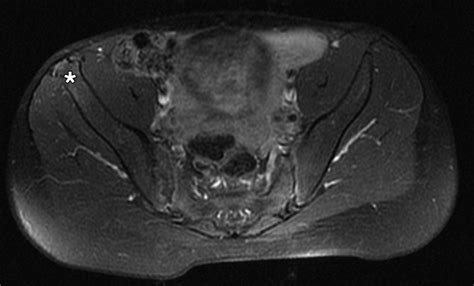

Diagnosing iliac crest apophysitis typically involves a combination of a physical examination and medical history. A healthcare provider will assess the symptoms and perform a physical exam to identify tenderness and swelling at the iliac crest. Imaging tests, such as X-rays or MRI scans, may be ordered to rule out other potential causes of pain and to confirm the diagnosis.